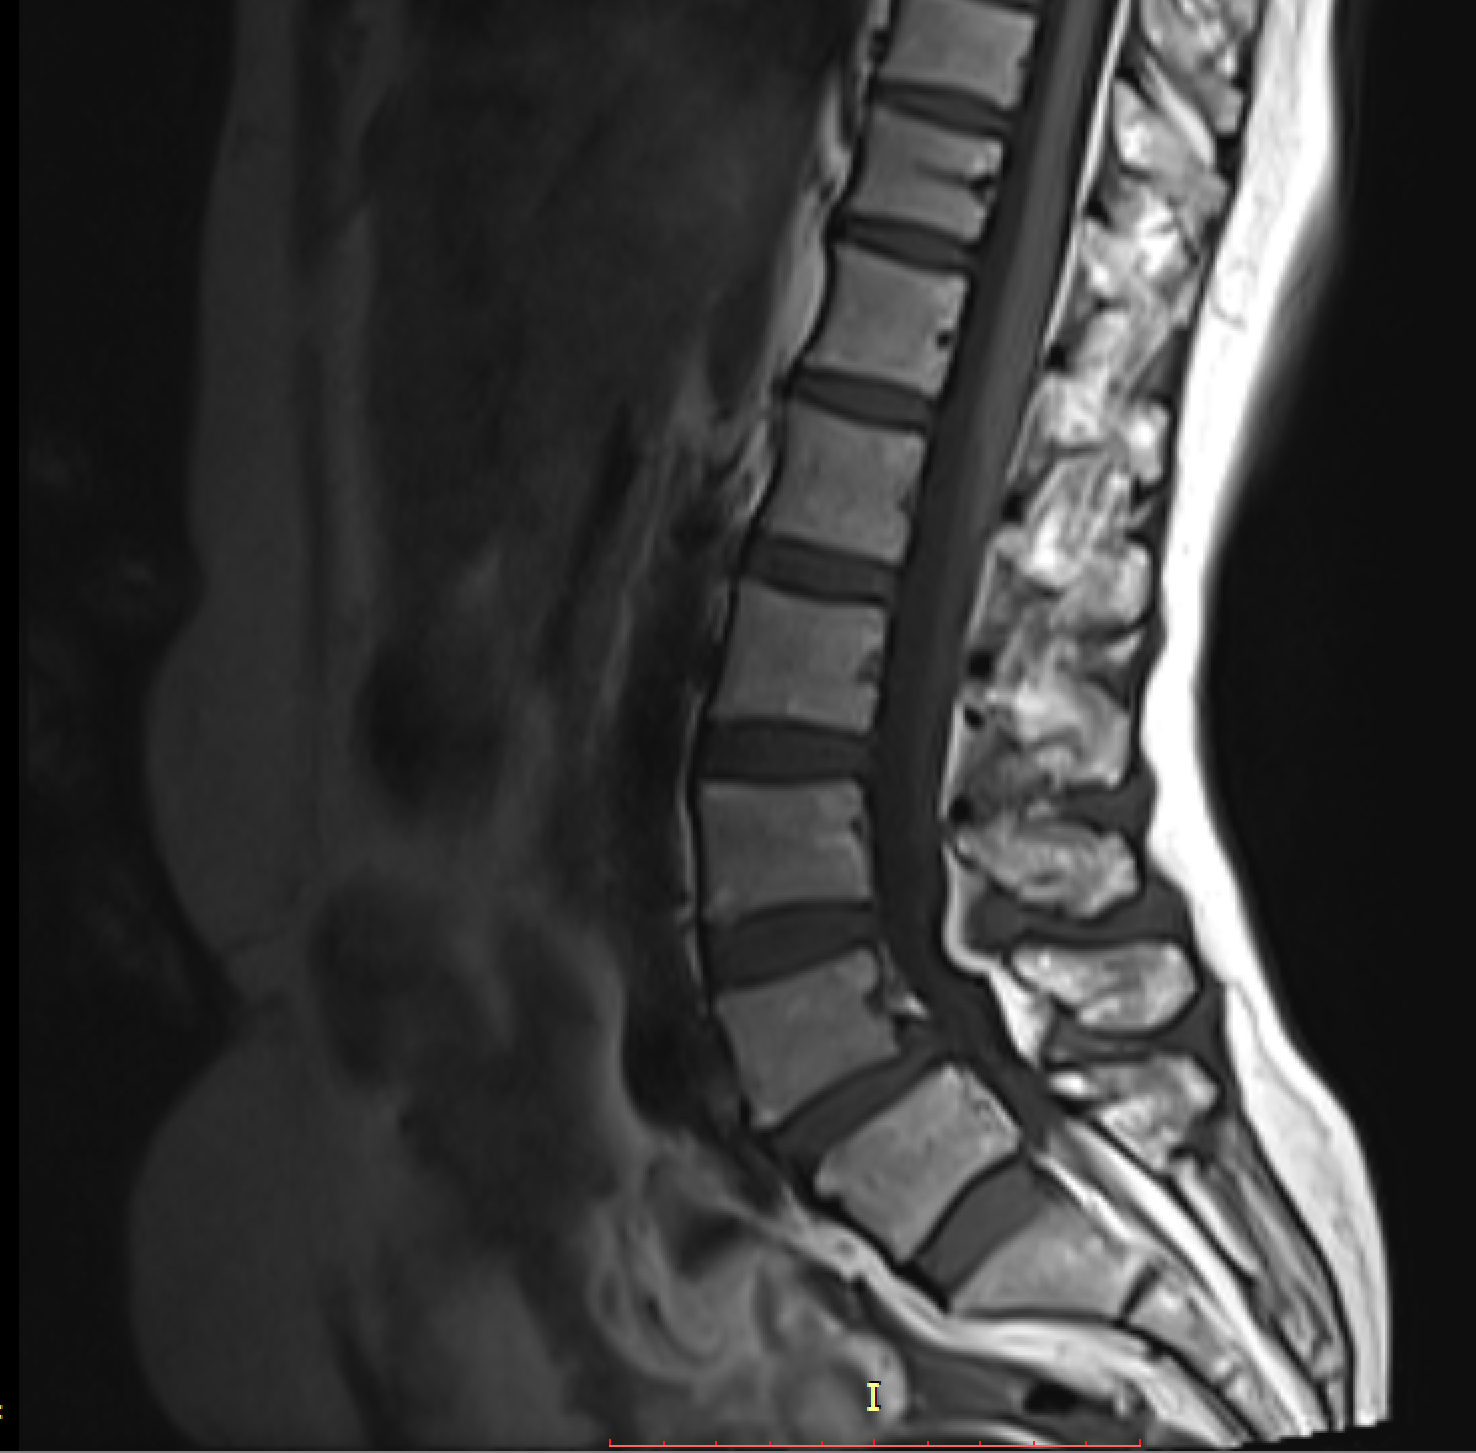

تشخیص پوکی استخوان از روی MRI

تشخیص هوشمند و زودهنگام پوکی استخوان با استفاده از اسکنهای دقیق MRI ستون فقرات کمری، برای شناسایی سریعتر و دقیقتر.

تشخیص سریع و قابل اعتماد که نیاز به آزمایشهای تهاجمی را کاهش داده و نتایج درمان بیمار را بهبود میبخشد.